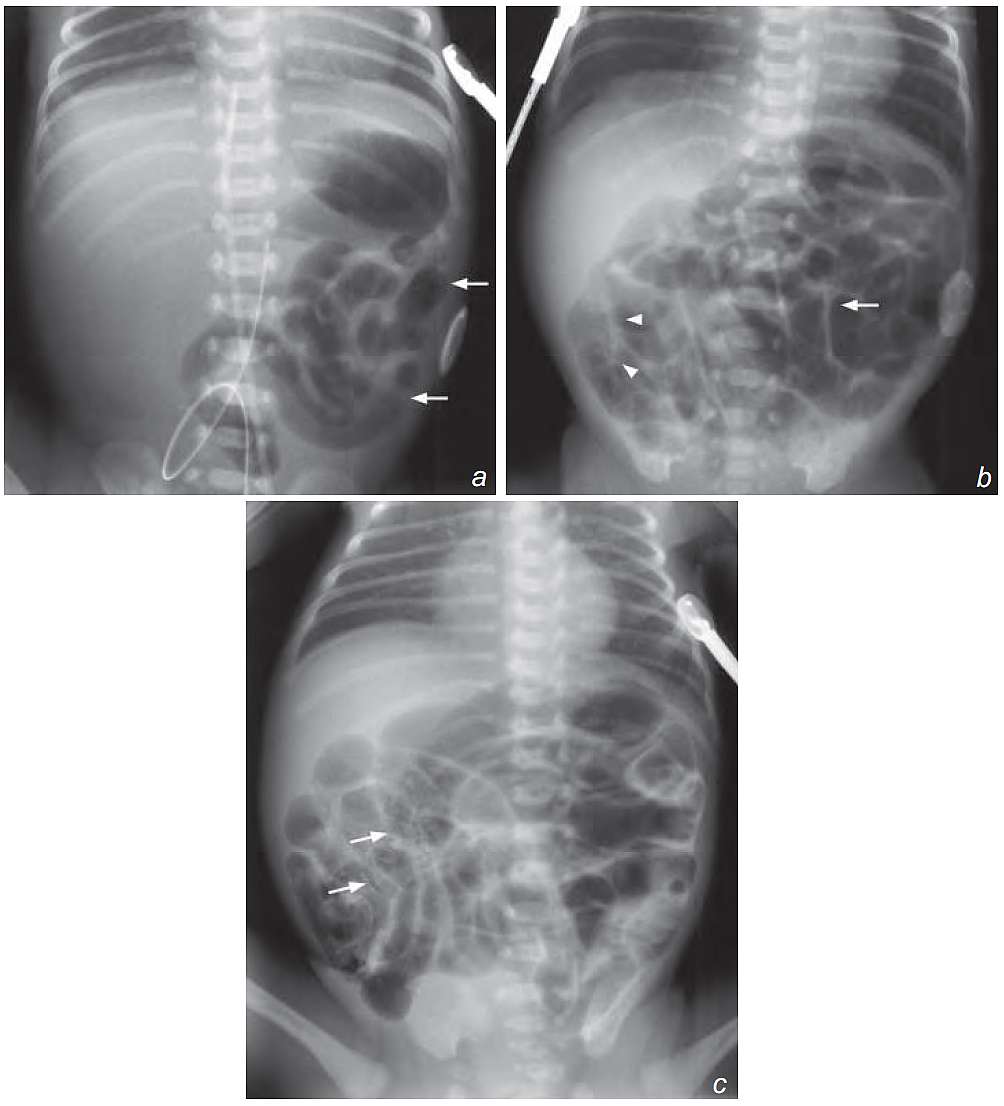

A 5-day-old premature neonate developed progressive abdominal distension and blood in stool after institution of oral feeding. He was septic on general examination, and the abdomen was distended and hyper-resonant on percussion. Bowel sounds were sluggish on auscultation.

Laboratory investigations showed raised white cell count and C-reactive protein. Blood culture grew Gram-negative organism.

What radiological abnormalities can you detect and what is the diagnosis ?